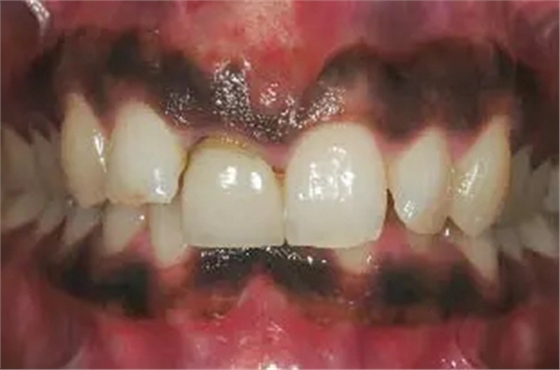

圖1、該病例顯示了厚齦生物型和中弧線形齦乳頭形態(tài)。右上中切牙由于牙根縱裂而需要拔除。由于該患牙伸長,使得軟組織量垂直向增加。牙齦色素沉著是個美學(xué)挑戰(zhàn)。